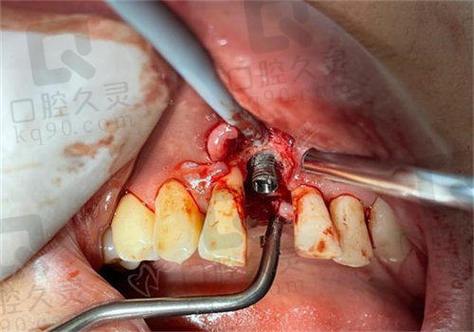

- 术区污染:手术器械消毒不彻底、术区口腔清洁不足,或术中操作导致唾液、细菌进入种植窝,引发种植体周围感染,破坏骨组织。

- 骨处理不充分:牙槽骨存在炎症、囊肿或纤维化组织未彻底清除,或术中产热过高(如钻速过快、未充分冷却),导致骨细胞坏死,形成“死骨区”。

- 感染控制:若为种植体周围炎,需先进行清创(刮除感染组织)、冲洗,并全身或局部使用抗生素;若感染严重,需取出种植体,待炎症完全控制(通常2-4周)后再评估。

- 取出种植体:对于松动明显、骨吸收严重的种植体,需及时取出,避免残留种植体碎屑影响骨愈合,取出后彻底清理种植窝,去除炎性肉芽组织。